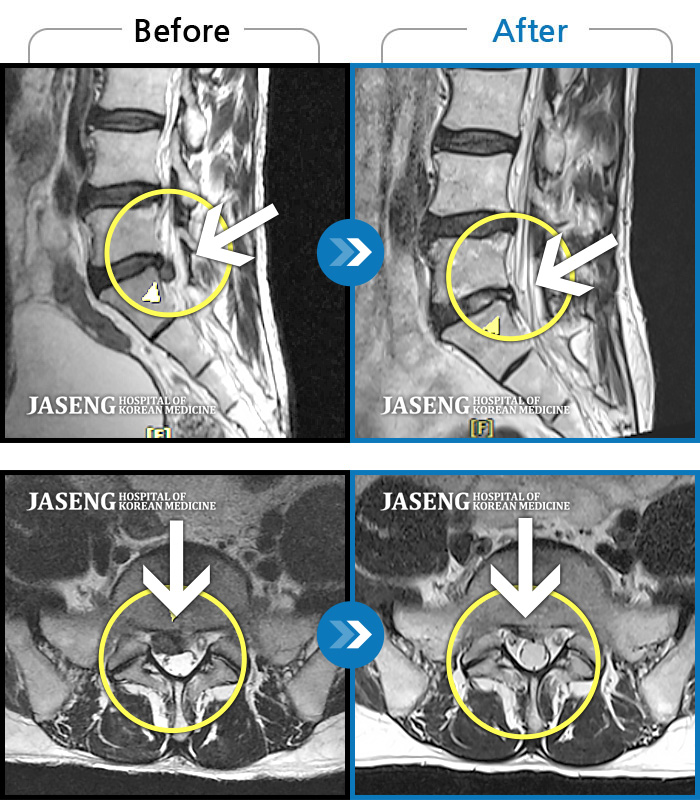

Before

After

환자에게 사전 동의를 받아 동일 조건에서 촬영되었습니다.

개인에 따라 치료 후 부작용이 발생할 수 있으니 의료진과 상담 후 치료를 진행하시기 바랍니다.

허리 통증과 오른쪽 다리 당김

허리 양측 둔부에서 발가락으로 통증, 비증, 힘이 빠지는 증상